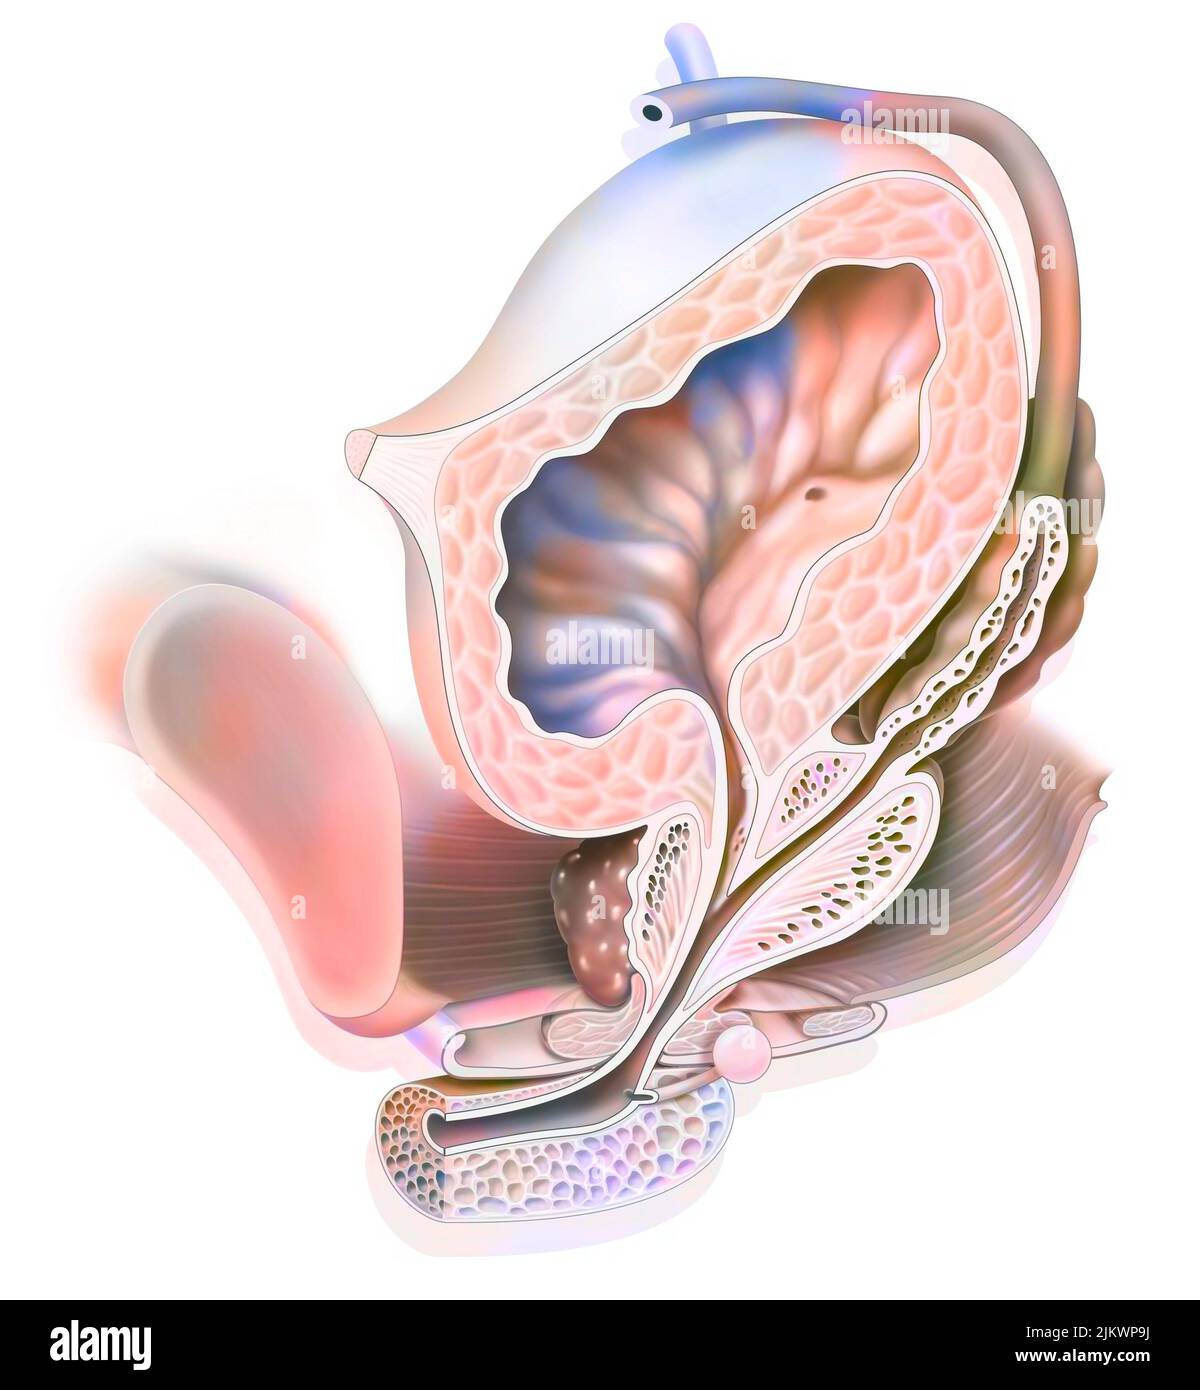

RF2PMGJB9–Männliche Fortpflanzungssysteme auf weißem Hintergrund. Vektordarstellung männlicher Fortpflanzungssysteme